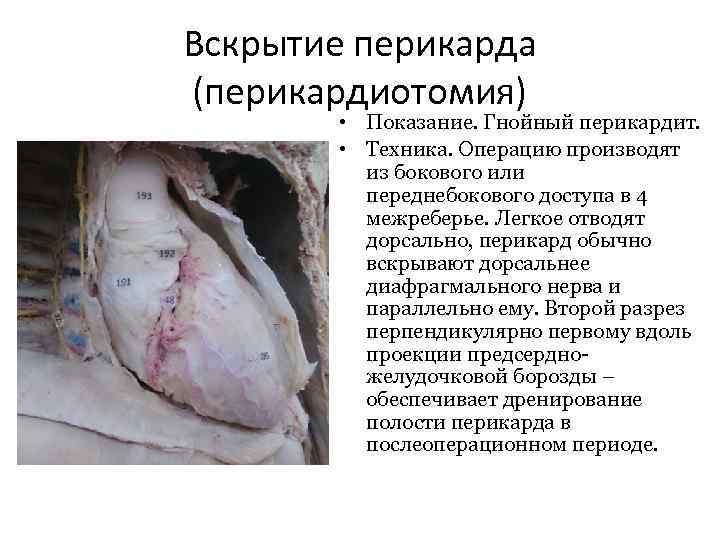

Вскрытие перикарда (перикардиотомия) • Показание. Гнойный перикардит. • Техника. Операцию производят из бокового или переднебокового доступа в 4 межреберье. Легкое отводят дорсально, перикард обычно вскрывают дорсальнее диафрагмального нерва и параллельно ему. Второй разрез перпендикулярно первому вдоль проекции предсердножелудочковой борозды – обеспечивает дренирование полости перикарда в послеоперационном периоде.

Вскрытие перикарда (перикардиотомия) • Показание. Гнойный перикардит. • Техника. Операцию производят из бокового или переднебокового доступа в 4 межреберье. Легкое отводят дорсально, перикард обычно вскрывают дорсальнее диафрагмального нерва и параллельно ему. Второй разрез перпендикулярно первому вдоль проекции предсердножелудочковой борозды – обеспечивает дренирование полости перикарда в послеоперационном периоде.

Перикард вскрыт продольным и перпендикулярным к диафрагмальному нерву разрезами. Производят интраоперационную ревизию сердца. При резком стенозе левого предсердно-желудочкового клапана – расширенное левое предсердие с увеличенным ушком.

Перикард вскрыт продольным и перпендикулярным к диафрагмальному нерву разрезами. Производят интраоперационную ревизию сердца. При резком стенозе левого предсердно-желудочкового клапана – расширенное левое предсердие с увеличенным ушком.

После опорожнения полости перикарда в рану вставляют резиновый дренаж, края раны сближают редкими швами.

После опорожнения полости перикарда в рану вставляют резиновый дренаж, края раны сближают редкими швами.